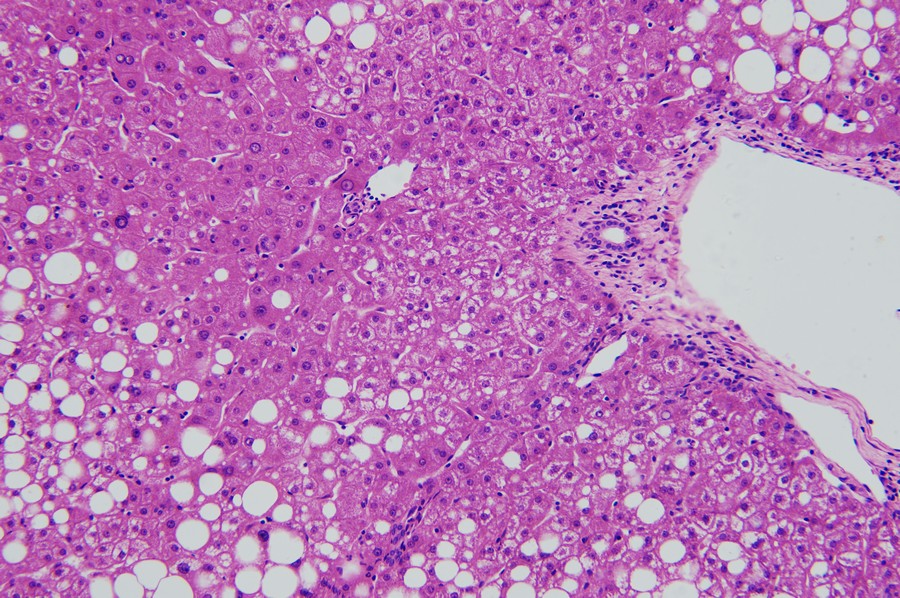

ML31下的脂肪肝:小空泡

当肝细胞出现脂肪变性,镜下可见细胞内出现大小不一空泡,早期主要在细胞核周围形成小空泡。

ML31下的脂肪肝:大空泡

随着情况加重,空泡会增多合并形成大空泡,空泡占比越高,脂肪肝情况越严重。

ML31下的脂肪肝:肝细胞气球样变

在这个视野中我们还可以看到肝细胞的气球样变,显示肝细胞受损进展中。当肝细胞受损后,水分增多会引起肝细胞胀大、胞浆疏松化,进一步发展肝细胞胀大如球形,胞浆几乎透明,这就是肝细胞的气球样变。